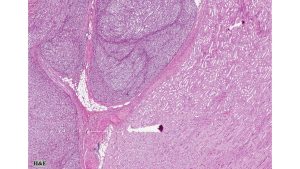

A 38-year-old male presented with a history of persisting right flank pain. Ultrasonography revealed a 10 cm mass in the mid-portion of the right kidney at the corticomedullary junction. A CT-guided biopsy revealed a spindle cell neoplasm of uncertain malignancy. The patient underwent a right nephrectomy, which revealed a 10×6×5 cm solid tumor with vascular invasion. On gross examination, the tumor was grayish white with areas of hemorrhage and necrosis.

Histologic examination revealed densely cellular fascicles of monomorphic spindle cells with indistinct borders, oval nuclei and scant cytoplasm. The background showed necrosis and areas of hemorrhage. Immunohistochemical analysis revealed tumor cells positive for vimentin, CD99, BCL-2 and TLE1, while negative for CEA, EMA, desmin, chromogranin, synaptophysin, enolase, S-100, CD10, CD117, Caldesmon, beta-catenin, PAX2, and WT-1.

Primary synovial sarcoma of the kidney is exceedingly rare and often presents a diagnostic challenge due to morphologic overlap with other renal spindle cell tumors, such as sarcomatoid renal cell carcinoma, sarcomatoid urothelial carcinoma, and other primary renal sarcomas (e.g., leiomyosarcoma or malignant peripheral nerve sheath tumor). The monophasic spindle cell variant lacks epithelial components, making differentiation particularly difficult without molecular testing. Immunohistochemistry often demonstrates expression of TLE1, CD99, vimentin, and BCL-2, but these markers are not entirely specific. The definitive diagnosis hinges on detecting the characteristic t(X;18)(p11;q11) translocation, which results in the SS18-SSX fusion (typically SSX1 or SSX2) via FISH or RT-PCR.. These tumors tend to behave aggressively, with potential for local recurrence and distant metastasis, particularly to the lungs and liver. Long-term follow-up is essential, and optimal management often requires a multidisciplinary approach, incorporating surgery and consideration of systemic therapy in selected cases.